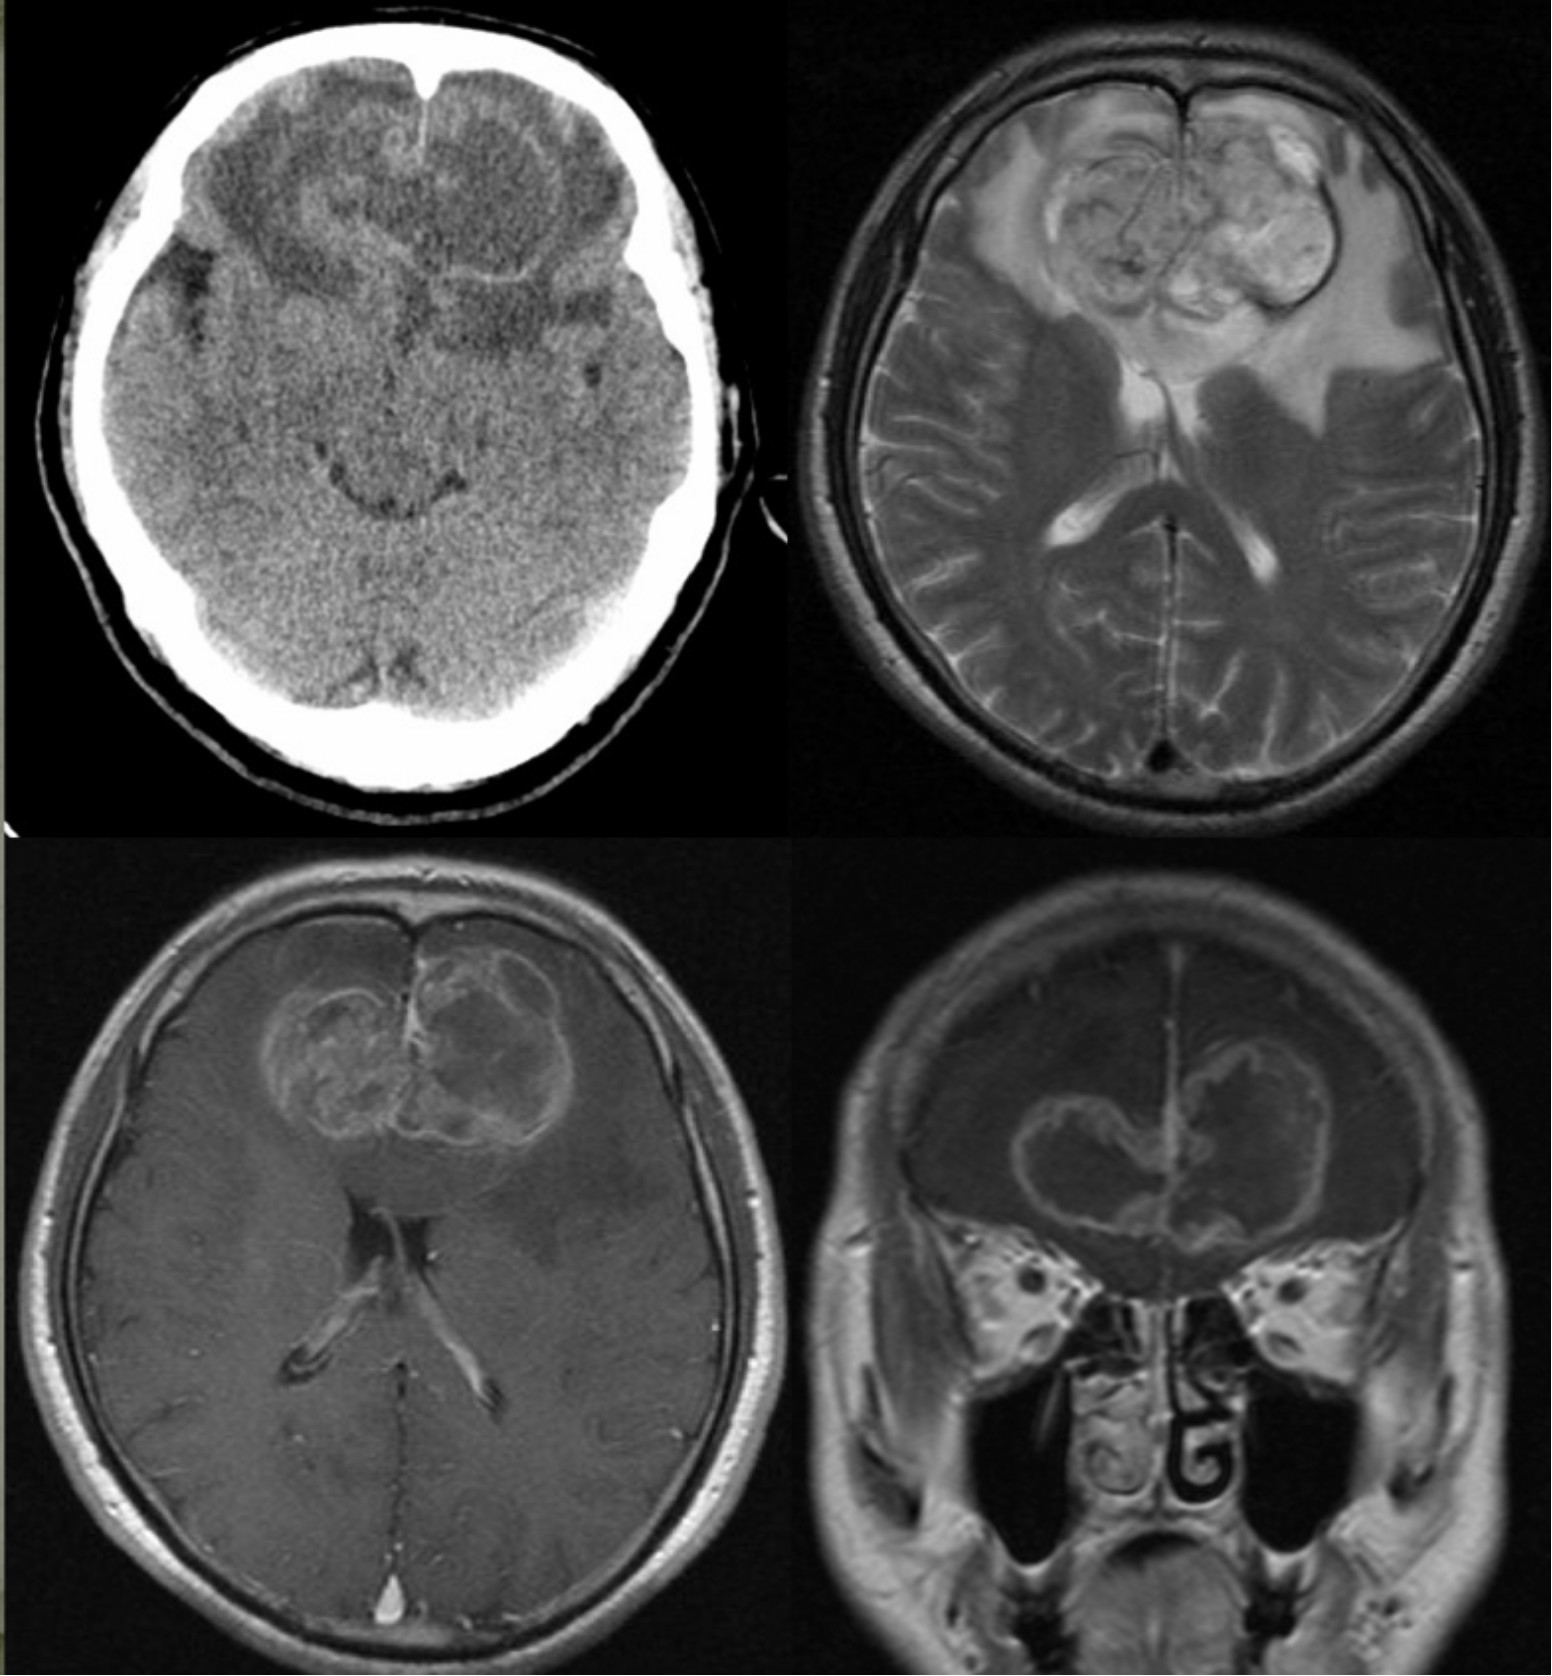

患者入院前3月来无明显诱因下逐步出现性格改变,主要表现为寡言少语,不关心家人。近1周上述情况明显加重,伴有言语错乱。当地医院就诊行头颅CT及MRI检查发现颅内占位病变(图1),为求进一步治疗来浙医二院就诊,门诊以“双额叶胶质瘤”收入院。

图1. 头颅CT提示双侧额叶占位病变,水肿及占位效应明显。MRI检查提示病变累及双侧额叶和胼胝体,T2WI显示病变周围水肿明显,T1WI增强提示肿瘤明显不均匀强化。